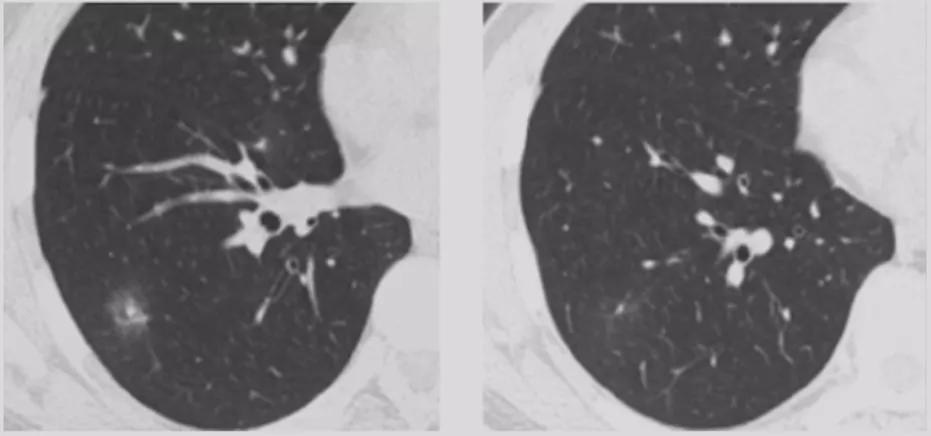

内部特征:支气管充气征

支气管充气征可能表现为各种形式,支气管被肿瘤组织包挠,未完全塌陷,或瘤组织在细支气管表面呈附壁式生长而不充盈管腔,也可为扩张的细支气管。

这是几种特殊类型的支气管充气征:

Ⅰ型和Ⅱ型做导航的话结果都非常好。对于各种各样的支气管征象来说,现在有分型软件,可以进行三维重建,作为一个非常重要的指标。因此,我们观察结节,不能光从一个层面看,要从多个层面去观察气管、血管等多个的征象的变化。